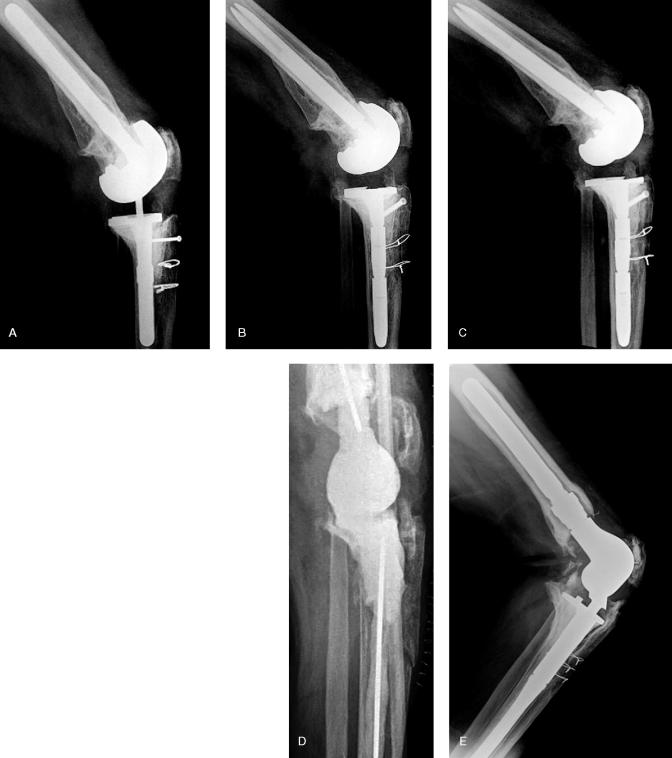

Tibial tubercle osteotomy (TTO) is an established surgical technique for exposing the stiff kneein revision total knee arthroplasty (RTKA). The osteotomy is usually performed through the anterior metaphyseal cancellous bone of the tibia but it can be extended into the intramedullary canal if tibial stem and cement removal are necessary. Furthermore, repeat osteotomy may be required in another RTKA. We assessed whether intramedullary extension of TTO or repeat osteotomy affected the healing rate in RTKA.

We retrospectively evaluated 74 consecutive patients (39 women) with an average age of 60 (29-89) years who underwent 87 TTOs during RTKA. 1 patient had bilateral TTO.10 patients had repeat TTO and 1 patient received 3 TTOs in the same knee. The osteotomy was extramedullary in 57 knees and intramedullary in 30 knees. Osteotomy repair was performed with bicortical screws and/or wires.

Bone healing occurred in all the cases. The median time to union was 15 (6-47) weeks. The median healing time for the extramedullary osteotomy group was 12 weeks and for the intramedullary osteotomy group it was 21 weeks (p = 0.002). Repeat osteotomy was not associated with delayed union. Neither intramedullary nor repeat osteotomy was found to increase the complication rate of the procedure.